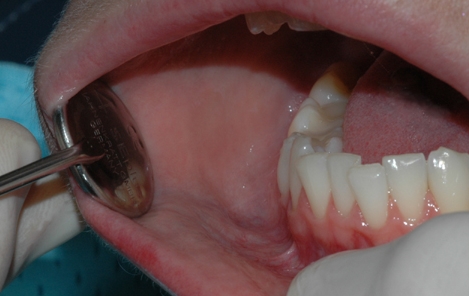

Tannlegen undersøker hver enkelt tann etter hull og skader

Tannkjøttet og tennenes benfeste blir vurdert